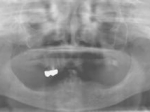

両側5歯症例

両側5歯症例両側5歯症例両側5歯症例 主訴-義歯のバネが壊れて手前の歯が痛んできた。 術前(旧義歯装着、鏡像) 術前(下顎粘膜面、鏡像)術前(下顎粘膜面、鏡像)術前(下顎粘膜面、鏡像) 術前レントゲン術前レントゲン術前レントゲン 術前口腔内(正面観)術前口腔内(正面観)術前口腔内(正面観)

術後(鏡像)術後(鏡像)術後(鏡像) 術後口腔内(正面観)術後口腔内(正面観)術後口腔内(正面観)もう入れ歯は要らなくなりました。 術後レントゲン術後レントゲン術後レントゲン